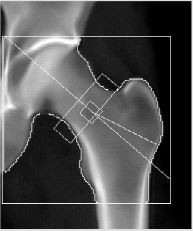

| 腰椎+股関節 | 1,390円 |

年齢を重ねると、腰椎は次のような変化の影響で、実際より骨密度が高く測定されることがあります。

当院では、より正確な評価のため 「腰椎+股関節」を標準としてご案内しております。 |

![]() 大腿骨画像 |